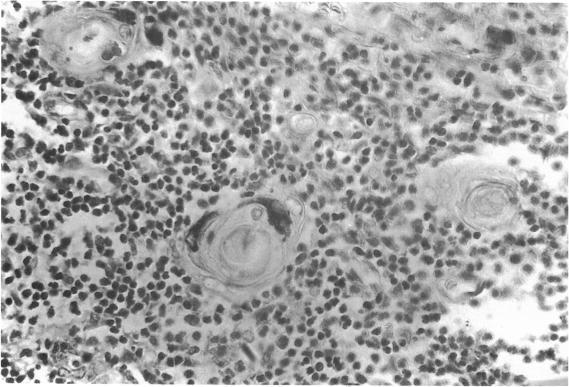

人胸腺哈氏小体内的免疫球蛋白

Immunoglobulins in Hassall's corpuscles of the human thymus.

Ninety nine human thymuses were examined immunohistochemically for the presence of immunoglobulins G, A, M. D and E, light-chains, secretory component and albumin in the cells of Hassall's corpuscles. Igs G, A, M and secretory component were present. These showed a rise after birth until the age of 20 years and also increased with the degree of involution, falling when involution became complete. Albumin was also consistently demonstrated. There was a degree of correlation between the presence of Igs and production of Igs G, A and M by plasma cells in the thymic medulla. There was a close correlation between the amounts of IgA and secretory component in the cells of Hassall's corpuscles and the thymus may have to be regarded as a part of the secretory-IgA system. Light chains of the immunoglobulin molecule were also present, with lambda predominating over kappa, possibly reflecting the same kappa/lambda ratio found with thymic immunoglobulin production. No IgD or IgE was demonstrated. The presence of albumin may represent a passive uptake of protein in senescent cells but a more active uptake of Igs, particularly IgG and IgA, could be postulated. The production of Igs in the thymus and their presence in Hassall's corpuscles could be of significance in the maturation and regulation of the immune response.

摘要